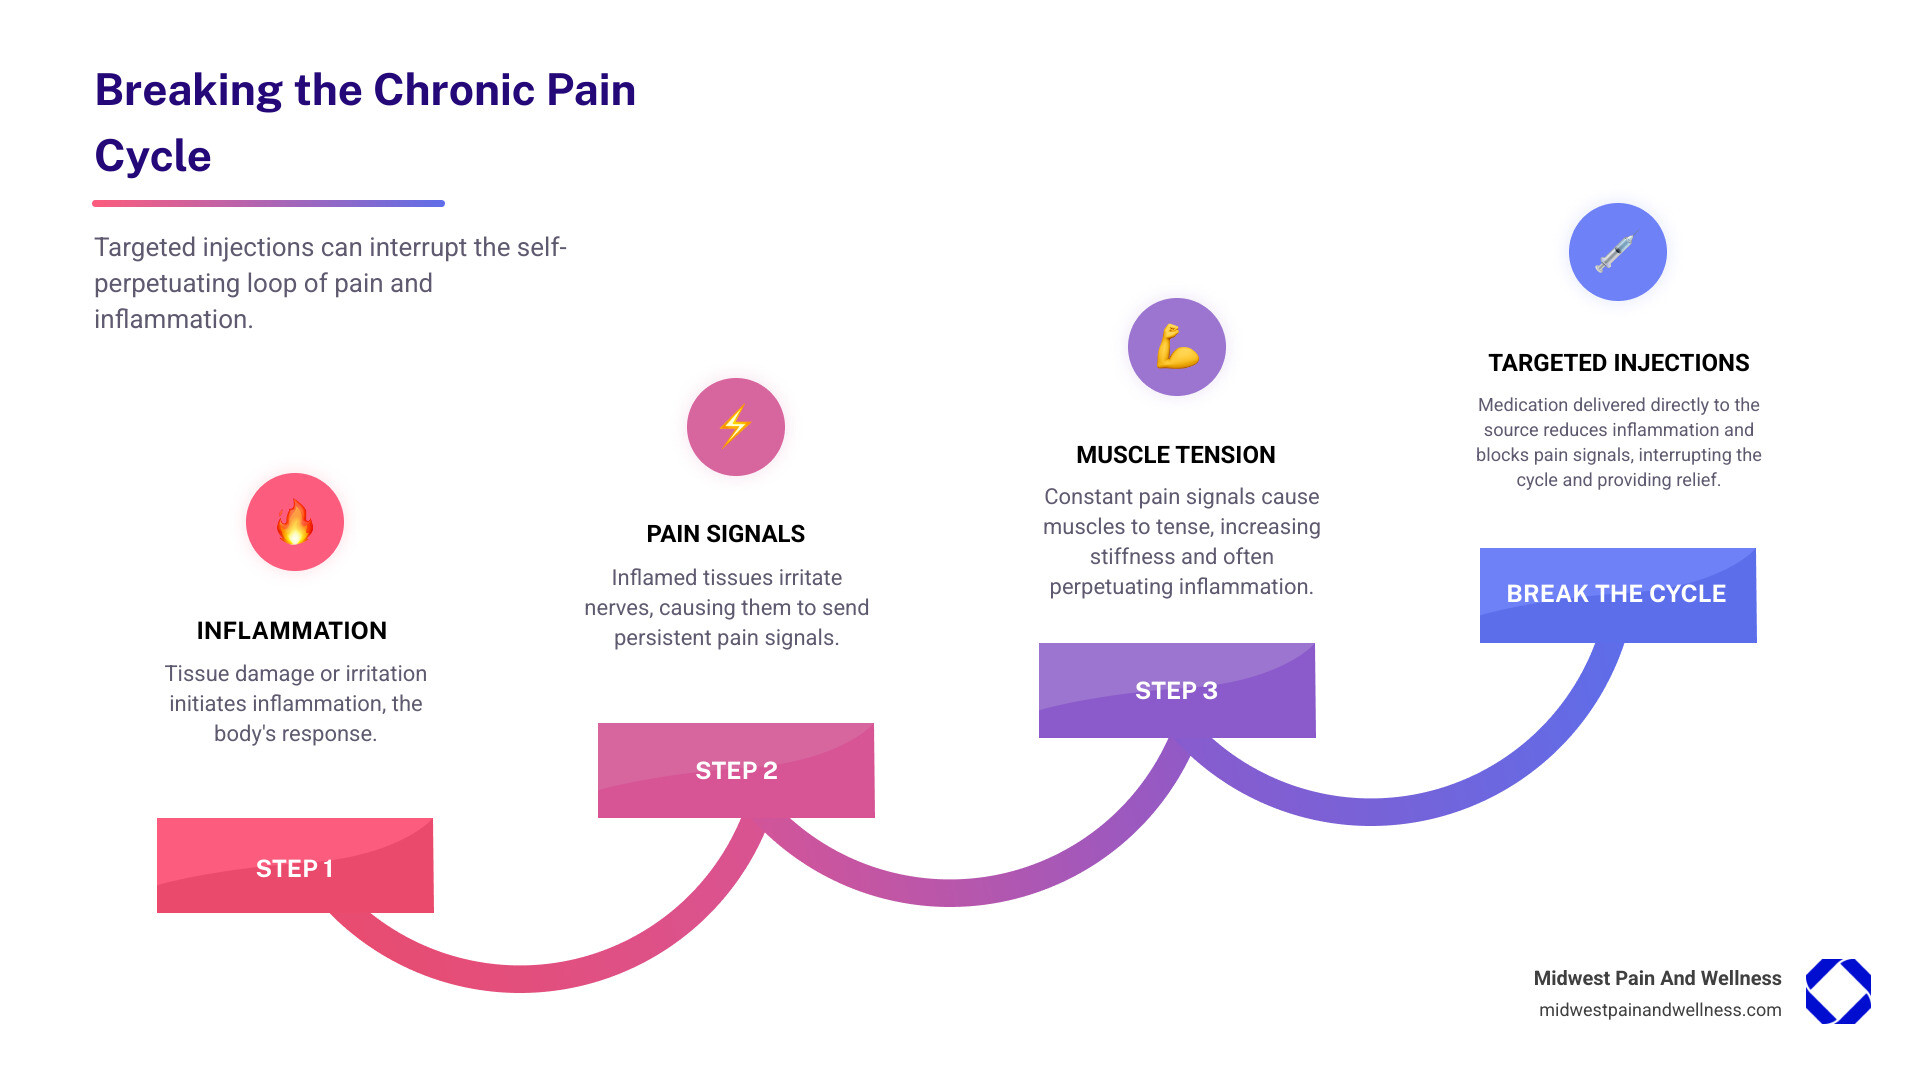

Chronic pain affects millions, disrupting sleep, limiting mobility, and draining the joy from daily activities. When oral medications aren’t enough and surgery feels too drastic, pain injections offer a middle path. These minimally invasive procedures deliver medication directly to the source of your pain, providing both immediate relief and long-term inflammation reduction.

Instead of just masking pain with oral pills, pain injections deliver medication directly to the source of your discomfort. This modern approach is a strategic tool designed to reduce inflammation, interrupt pain signals, and promote healing by getting to the root of the problem.

Pain injections deliver medication directly to the specific area causing your pain. Unlike pills that circulate throughout your body, this targeted approach provides more powerful relief with fewer side effects.

These injections often use a combination of medications:

- Anesthetics: Provide immediate relief by numbing nearby nerves and blocking pain signals from reaching your brain.

- Corticosteroids: These are strong anti-inflammatory medications that calm swelling and irritation, creating a better environment for healing and offering longer-lasting relief.

This combination provides therapeutic relief and also serves a diagnostic purpose. If an injection brings significant relief, it helps confirm that the targeted area was the source of your pain, which is crucial for planning long-term care. This direct intervention can often help patients avoid more invasive procedures like surgery. To learn more about how we use this therapy, explore more info about injection therapy.